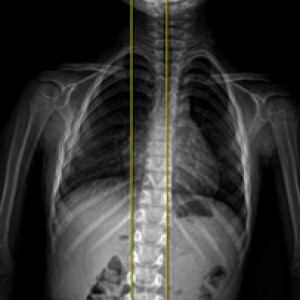

검사부터 다른 당당

“당당은 뼈만 보지 않습니다.”

근육과 근막의 정렬을 함께 진단하며, 풀 스파인 촬영을 통해 머리부터 모든 고관절, 발의 정렬까지 함께 파악하여 개개인에 맞는 전신 치료법을 설계합니다.

디테일하게 자세 패턴을 분석합니다.

7가지 패턴으로

정확한 진단을 합니다.

더 다양한 패턴을 바탕으로 분석 후 계획을 세우기 때문에, 진단과 치료의 정밀도가 다릅니다.

신체 부위별 틀어진 방향, 각도에 따라 카테고리별로 분류한 후, 그에 맞는 치료법을 실시합니다.

전신 엑스레이 검사